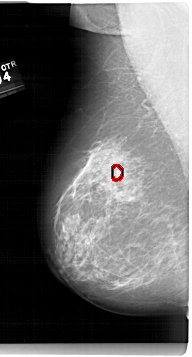

A_1679_1.LEFT_MLO

LEFT_MLO LINES 6781 PIXELS_PER_LINE 3631 BITS_PER_PIXEL 12 RESOLUTION 43.5 OVERLAY

FILE: A_1679_1.LEFT_MLO.OVERLAY

TOTAL_ABNORMALITIES 1

ABNORMALITY 1

LESION_TYPE MASS SHAPE LOBULATED MARGINS OBSCURED-CIRCUMSCRIBED

ASSESSMENT 4

SUBTLETY 3

PATHOLOGY BENIGN

TOTAL_OUTLINES 1

BOUNDARY